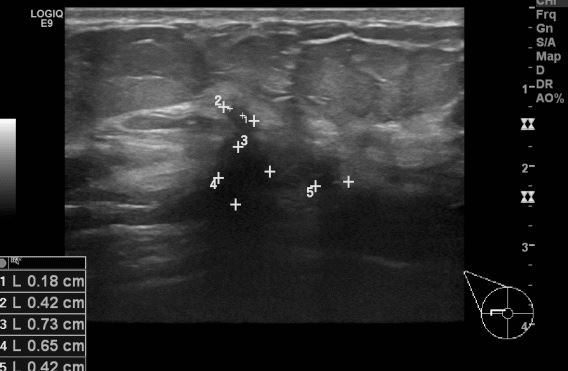

상기환자 건강검진상 이상 소견으로 내원하신 50대 여성분으로 본원초음파상

우측 상외측 의심스러운 멍울 조직검사 시행하여 우측 침윤성 유관암진단되었습니다.